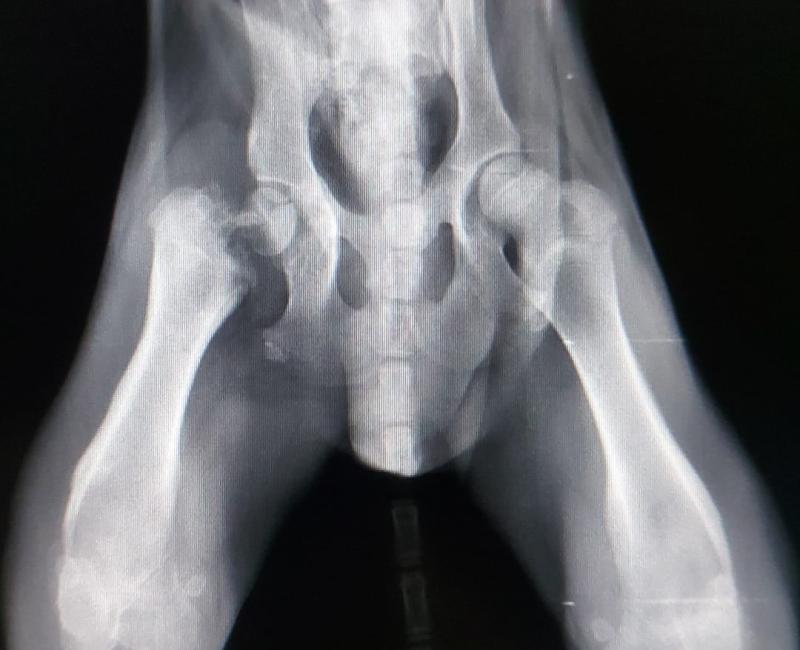

Ya le habían realizado placas y necesita una operación, puesto que tiene dos lesiones diferentes. Hay una osteolísis de la cabeza femoral derecha y una osteodistrofia hipertrófica de las epífisis distales de ambos fémures. Así que tenemos que extirpar la cabeza del fémur de una de las patas.

03 Junio de 2021: Kangaroo ya pasó por quirófano para retirarle la cabeza del fémur, por una malformación le estaba dando mucho la lata. El pobre no tiene nada de masa muscular pero esta con la mejor de las acogidas que podía tener: ¡una de sus veterinarias!. Le está haciendo rehabilitación e hidroterapia. Seguro que esa pata se pone perfecta en 4 días.